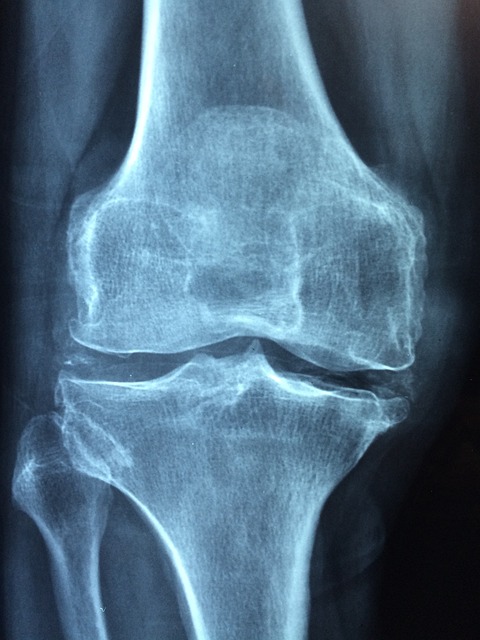

최근 엄마가 골다공증 검사를 받았습니다. 작년에는 골다공증 T-스코어 수치가 -2.7 이었는데, 이번엔 새로 한 결과에서는 -3.0으로 더욱 심각해졌어요. 이는 심한 골다공증 상태로 간주되며, 골절 위험이 매우 높기 때문에 적극적인 치료와 관리가 필요하다고 하네요. 골다공증 T-스코어 수치, 약물치료방법, 골다공증에 좋은 음식과 영양제, 운동요법과 생활습관 관리에 대해 종합적으로 알아보겠습니다.

T-스코어는 개인의 골밀도를 건강한 20~30대 젊은 성인의 평균 골밀도와 비교한 값입니다. 골밀도(BMD, Bone Mineral Density)를 측정한 후, 표준편차(Standard Deviation, SD)를 기준으로 값을 나타냅니다.

WHO(세계보건기구)에서는 T-스코어를 기준으로 골다공증 여부를 진단합니다.

-1.0 이상 | 정상 | 골밀도가 정상 범위 |

-1.0 ~ -2.5 | 골감소증(골다공증 전 단계) | 골밀도가 감소했지만 골다공증은 아님 |

-2.5 이하 | 골다공증 | 골밀도가 심각하게 낮아 골절 위험 증가 |

-2.5 이하 + 골절 경험 | 심한 골다공증(중증 골다공증) | 골밀도가 매우 낮고 골절 위험이 높음 |